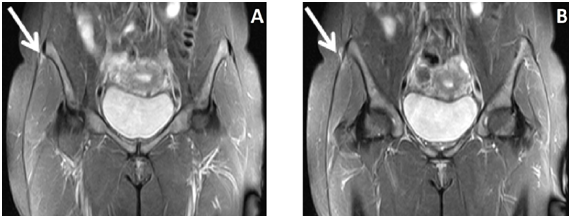

37-year-old woman, obese, with pain in the right hip, close to the iliac spine for 06 months, worsening at night. Works as a clerk and walks about 6 kilometers daily. Deny other traumas and physical activity. At physical examination, the patient reported pain on palpation of the iliac tubercle on the right and positive test on Ober's maneuver. Ely test and contracture test of the posterior thigh muscles negative. No edema or bruising at the site of pain inspection. MRI demonstrated swelling around the right anterior iliac spine and sign change of the iliotibial band inserting, compatible with proximal iliotibial band syndrome (Figures 1 & 2). With the diagnosis, the patient was advised to perform rest, treatment with anti-inflammatory and physical therapy - shock wave therapy and muscle strengthening, in addition to diet for weight loss.

Figure 2 MRI T2 FAT SAT in axial section demonstrates edema around the anterior superior iliac spine and high signal in the right ITB, compatible with the proximal iliotibial tract syndrome (white arrow).

MRI demonstrates signal increase in T2 STIR sequences around the insertion of the iliotibial band in the iliac tubercle and may also show partial thickening and / or partial rupture of its proximal insertion.4 Bone edema of the iliac tubercle is uncommon.4 All patients reported in the literature responded to resting and physiotherapeutic treatment for stretching and muscle strengthening of IBT, in addition to anti-inflammatories.1,4